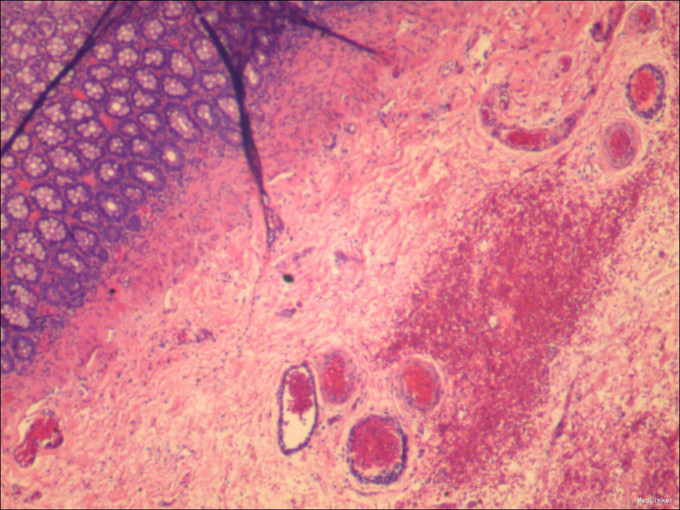

诊断:肛门狭窄术后继发性巨结肠 治疗:完善术前准备,全麻下行腹腔镜下经肛门继发性巨结肠根治术,术中见肛门往内回缩,肛周瘢痕增生明显,直肠下段扩张明显,术后给予积极抗感染补液治疗。